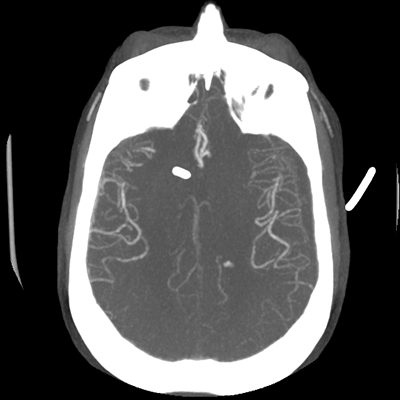

CTA head (MIP)

Starting with the non-contrast head CT, we can appreciate that there's actually not much residual subarachnoid blood at all; it's essentially all resorbed already (and cleared through the EVD). The ventricular caliber is stable. With the CTA head (for convenience's sake, the MIPs were shown), it's subtle, but we can see that the PCAs on each side are not as smooth and regular. The right MCA, starting at the bifurcation, also becomes narrower. This is [radiographic] vasospasm. Now, looking at the CT perfusion-- specifically, the Tmax (MTT) map that were selected-- there's clearly some abnormality within the bilateral cerebellar hemispheres and occipital lobes. Not a lot, but it's there. Delving further into this map, we can appreciate that the areas of abnormality are mainly green, signifying that these areas have Tmax > 6 seconds. This is the threshold that is specific, not sensitive, for vasospasm.

Putting this all together, we have thus identified radiographic vasospasm with the vessel imaging, with perfusion abnormalities that are concordant with it. Does the area of vasospasm and hypoperfusion correlate with the patient's clinical exam?